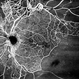

- OCT angiography of a 5-year-old male child with a history of laser therapy for retinopathy of prematurity, demonstrating the absence of macular FAZ (a), en-face images, fundus visualization, and increased macular retinal thickness.

- Xinyu Zhao, Shenzhen Eye Hospital, Shenzhen, China

Optical coherence tomography system

BM-400k BMi zar TowardPi Medical Technology. - Description